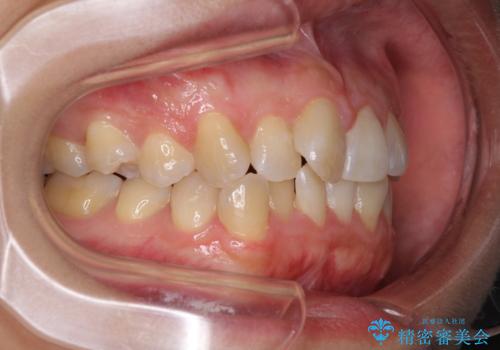

前歯のデコボコをインビザラインでスッキリと仕上げる

- 上下前歯のデコボコと奥歯の銀歯を気にして来院された患者様です。

口元をインビザラインにより歯列を整え、その後に失活している奥歯をオールセラミッククラウンにて補綴治療することとしました。

長時間のマウスピース装着に協力いただき、自然な口元に仕上げることができました。

気になっていた銀歯もオールセラミッククラウンで本物の歯のようになり、患者様には大変満足していただきました。